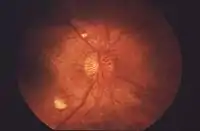

بقع الصوفي القطني (بالإنجليزية: Cotton wool spots) هي علامة طبية تظهر خلال فحص شبكية العين بالمنظار، وتظهر في شكل بقع بيضاء رقيقة على شبكية العين. تحدث بقع الصوف القطني بسبب تلف في الألياف العصبية، هذا التلف ناتج عن تراكم مواد سيتوبلازم المحور العصبي في طبقة الألياف العصبية، وهذا التراكم سببه انخفاض (نقص) في نقل المحور العصبي بسبب نقص التروية.

يؤدي تراكم مواد سيتوبلازم المحور العصبي إلى تلف الألياف العصبية من خلال وزمة الطبقة السطحية لشبكية العين. وقد خلص تحليل أجري عام 1981 إلى أنه "في معظم الحالات لا تمثل بقع الصوف القطني كل مساحة الشبكية التي تعاني من نقص التروية، ولكنها تعكس فقط عرقلة التدفق المحوري في المحاور المتقاطعة إلى مناطق نقص تروية أكبر بكثير".[1]

قد يصاحب وجود بقع الصوف القطني علامات أخرى مثل احتشاءات وعائية ونزيف بالشبكية. وقد ينخفض ظهور بقع الصوف القطني بمرور الوقت. فيما تظهر بقع الصوف القطني بشكل وفير في مرض ارتفاع ضغط الدم الخبيث.